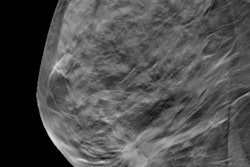

CHICAGO - Digital breast tomosynthesis (DBT) maintains its high performance over time when it comes to decreasing recalls and increasing the cancer detection rate, compared with 2D mammography alone, researchers from the University of Pennsylvania have found.

The study further confirms the technology's place in the breast cancer screening arsenal, according to results presented by Dr. Emily Conant at the RSNA meeting. She and colleagues analyzed DBT screening outcome data from the population level by year and the patient level by round over a six-year period.

"We found that at the population level, that is, everyone who comes for screening in a particular year, DBT increases the overall cancer detection rate and decreases the recall rate compared to 2D mammography, and that this outcome recurs over many years," she told AuntMinnie.com. "At the patient level, we found that successive rounds of tomosynthesis lowered recall rates, improving specificity."